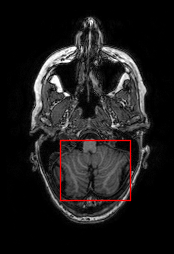

Sparsity Ikzsubscriptsuperscript𝐼𝑧absent𝑘I^{z}_{\downarrow k} LI 2D CNN 3D CNN Ours GT Ikz+1subscriptsuperscript𝐼𝑧1absent𝑘I^{z+1}_{\downarrow k}

4 Refer to caption Refer to caption Refer to caption Refer to caption Refer to caption Refer to caption Refer to caption

Refer to caption Refer to caption (a) 27.37/0.8465 Refer to caption (b) 32.34/0.9441 Refer to caption (c) 32.72/0.9436 Refer to caption (d) 34.11/0.9607 Refer to caption (e) PSNR(dB)/SSIM Refer to caption

8 Refer to caption Refer to caption Refer to caption Refer to caption Refer to caption Refer to caption Refer to caption

Refer to caption Refer to caption (f) 25.51/0.7681 Refer to caption (g) 28.29/0.8205 Refer to caption (h) 29.51/0.8824 Refer to caption (i) 31.87/0.9249 Refer to caption (j) PSNR(dB)/SSIM Refer to caption

Figure 5: Visual comparisons of slice interpolation approaches. For 4x sparsity, the second of three interpolated MR slices is presented. For 8x sparsity, the third of seven interpolated slices is presented.

5.3 Visual Comparisons

In Fig. 5, we present the observed slices Ikzsuperscriptsubscript𝐼absent𝑘𝑧I_{\downarrow k}^{z} and Ikz+1superscriptsubscript𝐼absent𝑘𝑧1I_{\downarrow k}^{z+1} along with the interpolated slices produced by different methods. Specifically we demonstrate the second of three interpolated MR slices for 4x sparsity, and the third of seven interpolated slices for 8x sparsity. We highlight the region where the anatomical structures significantly change compared to the observed slices Ikzsubscriptsuperscript𝐼𝑧absent𝑘I^{z}_{\downarrow k} and Ikz+1subscriptsuperscript𝐼𝑧1absent𝑘I^{z+1}_{\downarrow k}. We observe that although 2D CNN has comparable performance in terms of PSNR and SSIM, it tends to produce false anatomical structures in the zoomed regions. 3D CNN is able to resolve more accurate details. However, the improvement is quite limited, which we attribute to the fact that 3D CNN requires more training MR volumes in order to generalize and has smaller receptive field due to patch-based training. Our method benefits from the large receptive field of 2D CNN and two-view fusion, which not only produces sharper images, but also correctly estimates brain anatomy. The sharp and accurate estimation is crucial in clinical applications such as diagnosing Alzheimer’s Disease by brain volume estimation.